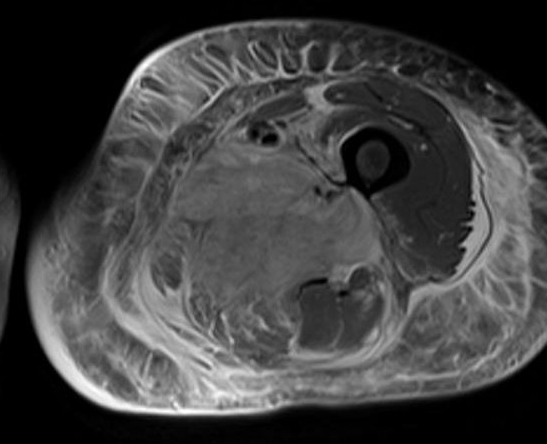

일반적인 X-ray 사진을 찍으면 단면으로 나오는데 CT 촬영을 하게 되면 원형으로 된 큰 기계 안에 들어가 X-ray 촬영을 하는 것으로 볼 수 있습니다. 몸을 가로로 잘라서 그 가로면을 평면적으로 볼 수 있게 됩니다.

X선과 컴퓨터를 결합한 촬영입니다. X선 즉 방사선 발생장치가 있는 큰 원형 기게 안에 들어가 컴퓨터 스캐너가 회전하면서 사람의 가로면 영상을 촬영해 영상을 만들어 냅니다.

사람의 몸 어느 부분이나 다 관찰할 수 있으며 누워 있는 사람을 중심으로 이 스캐너가 회전을 하면서 영상을 촬영하게 됩니다.